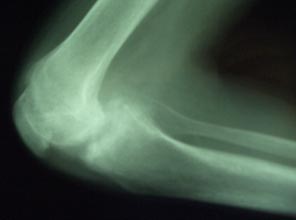

Full blood count revealed normal haemoglobin and white blood cell count. Chest X-ray was normal. Adequate knee X-rays were difficult to obtain and showed gross joint destruction with loss of joint space (Figs 2,3) and bone erosion. Radiologically and clinically the right knee was most severely affected. Testing for HIV was negative.

Figure 2: Plain lateral radiograph of the right knee.